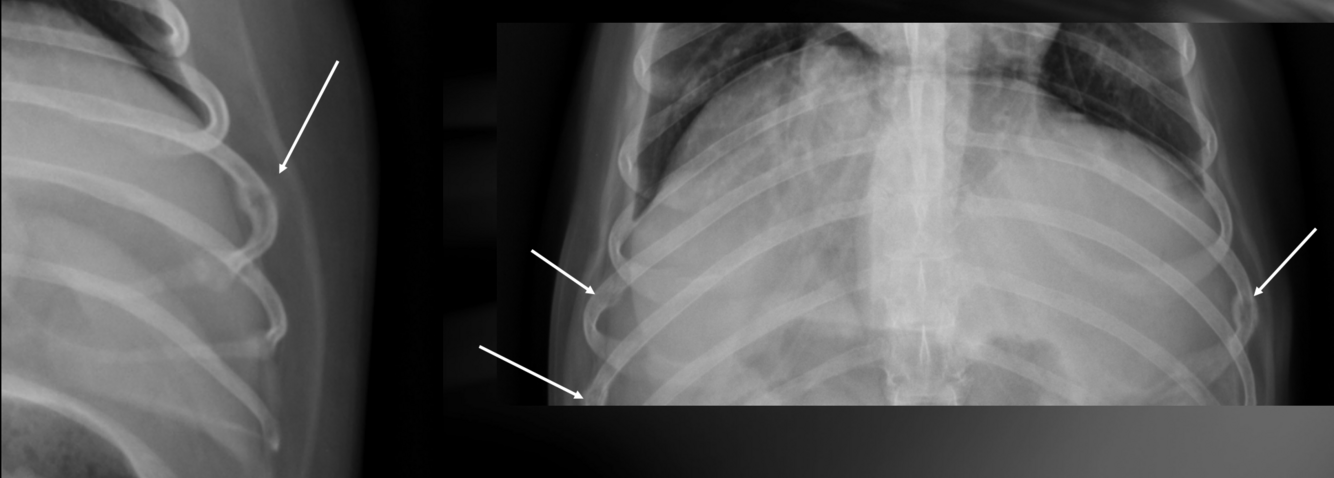

What is important regarding the ribs in these radiographs?

young dog; costal cartilages have not mineralized at all

middle-aged dog; costal cartilages have mineralized but not excessively

old dog; costal cartilages show irregular, exuberant mineralization